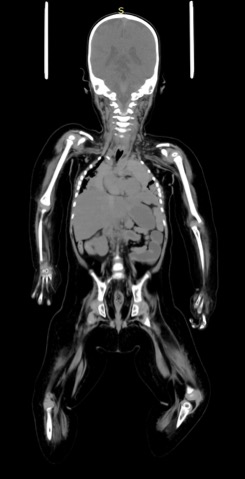

• (以下、AiCT)頭部は全身に比して小さい。 全身は軟部組織腫大の印象を受けるが、各部のバランスには異常を感じない。 筋は萎縮している。骨は細く slender bone の印象を受けるが、印象としては不動化による二次的なものとして納得できる程度と思われる。

• 外傷性変化は指摘できない。 全身の筋萎縮が高度である。皮下組織、腹腔内での脂肪組織量増大が認められる。脂肪組織の混濁が目立つ部分にはなく、浮腫性変化や皮下出血などが指摘できる部位はない。 管状骨は細くなっている。不動化の結果ではないかと思われる。腰椎は縦の長さが相対 的に目立ち、いわゆる tallvertebraである。脊柱の矢状方向の配列も乳児型であり、立位・ 歩行が確立していなかったことを示す。

• 重度の脳萎縮があり、全身の筋も著しく萎縮している。気切が行われており、気道は拡張して機械的呼吸補助下にあったことを示唆している。骨の形態からは長期仰臥位生活が示され、栄養摂取、水分摂取、排泄の管理棟も自力では行えず全介助の状態にあったと推測させる。

• 体幹や四肢の筋の萎縮が目立ち、四肢や肋骨が細い。ロクロニウムの継続投与の影響の可能性もあるが、脳機能とは別に筋肉性の異常があった可能性も考えられる。筋緊張が強かったことを考えると先天性筋強直性ジストロフィーなどの可能性もある。それが原因で、生後15日の心肺停止が起き、今回の死亡につながった可能性も考えられる。